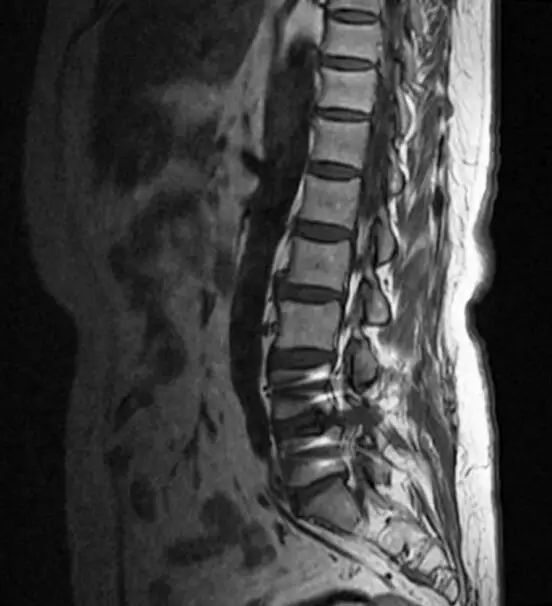

那么,节育环是否会产生伪影呢?这一点确实是真的,它确实会产生一些伪影并影响周围组织的图像质量。但是这种影响是局限在盆腔的,对于腰椎以及颈椎的核磁共振不会产生影响。以我今天门诊的一名50岁女性椎间盘突出患者为例,大家可以看到,X线片上显示盆腔里有金属节育器,在她的磁共振片子里,节育器确实产生了少量伪影,但是椎间盘突出的部位仍清晰可见,伪影未造成任何干扰,丝毫不影响医生的读片判断。

由此可见,体内有节育环的脊柱疾病患者可以放心大胆的做磁共振检查。另外,骨科的植入物由于在术中已被牢固地固定在骨骼和韧带、肌腱上,通常不会引起移动,因此是安全的,但和节育环一样,在做MRI检查时可产生伪影。比如下图,椎弓根钉就对脊柱椎管内的结构产生伪影干扰。